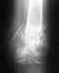

25 июля 09г. была получена при ДТП травма: открытый осколочный перелом обеих костей правой голени со смещением IIIB типа с разможжением мягих тканей.

Был установлен аппарат Илизарова. Выписан на 15й день. с 18.08.09 г. по 09.10.09 г. стационар- хронический остеомиелит обеих костей правой голени при не сросшемся переломе,обширный дефект мягких тканей. 1.02.10 г.по 24.02.10. операция по пересадке сложносоставного лоскута (торакодорсального) слева на микроанастомозах на правую голень.Аппарат Илизарова демонтирован. (были обильные гнойные выделения со всех болтов и из раны) 24.02.10.-12.03.10 некроз пересаженного лоскута по передней поверхности правой голени. Гнойный затек правой голени. Ложный сустав большеберцовой кости справа. Состояние после пластики тороко-дорзальным лоскутом. Операция 25.02- некроэктомия мягких тканей правой голени. вскрытие гнойных затеков. Операция 3.03.10.г.- Аутодермопластика раны правой голени. с 7го 10г. поднялась температура 39,6, держалась дней 5ть, ногу над раной разнесло с покраснением--рожа. Сейчас закончили прием амоксиклава и следом принимаем ципролет. Рана стала лучше. При движении ногой-нога волнообразно колышется и из отверстия выделяются желтые слизистые выделения и участок, где было оголено сухожилие-тоже выделения. В целом рана закрыта кожей. Фотографии и снимки прилагаем.Сейчас стоит вопрос: как зафиксировать кость? Да, пока у нас еще время для лечения рожистого воспаления. Но к чему готовиться? Ходим сами-ищем докторов.Потому что почти 7 месяцев в аппарате и не было никаких предложений. Сейчас-кто говорит ставить опять аппарат, кто-то советует поставить штифт с антибиотиком. А что делать дальше со свищем в ране? Хотим знать правильный правильный алгоритм дальнейшего лечения.

• Кликните для загрузки файла все снимкикопирование2.jpg

72KB (73815 bytes)